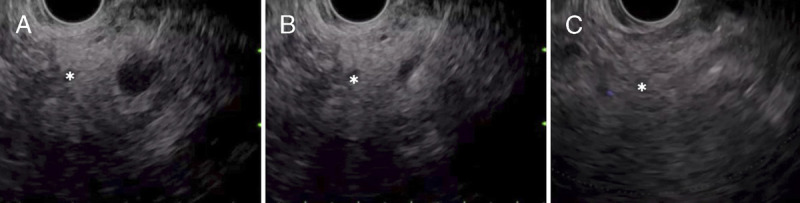

Hormonal changes revealed by selective arterial calcium injection tests in patients with insulinoma treated with EUS-guided ethanol injection.

{"title":"Hormonal changes revealed by selective arterial calcium injection tests in patients with insulinoma treated with EUS-guided ethanol injection.","authors":"Kazuyuki Matsumoto, Motoshi Komatsubara, Kenichi Inagaki, Hironari Kato, Motoyuki Otuka","doi":"10.1097/eus.0000000000000058","DOIUrl":null,"url":null,"abstract":"","PeriodicalId":11577,"journal":{"name":"Endoscopic Ultrasound","volume":"13 3","pages":"193-195"},"PeriodicalIF":5.4000,"publicationDate":"2024-05-01","publicationTypes":"Journal Article","fieldsOfStudy":null,"isOpenAccess":false,"openAccessPdf":"https://www.ncbi.nlm.nih.gov/pmc/articles/PMC11419466/pdf/","citationCount":"0","resultStr":null,"platform":"Semanticscholar","paperid":null,"PeriodicalName":"Endoscopic Ultrasound","FirstCategoryId":"3","ListUrlMain":"https://doi.org/10.1097/eus.0000000000000058","RegionNum":1,"RegionCategory":"医学","ArticlePicture":[],"TitleCN":null,"AbstractTextCN":null,"PMCID":null,"EPubDate":"2024/5/31 0:00:00","PubModel":"Epub","JCR":"Q1","JCRName":"GASTROENTEROLOGY & HEPATOLOGY","Score":null,"Total":0}